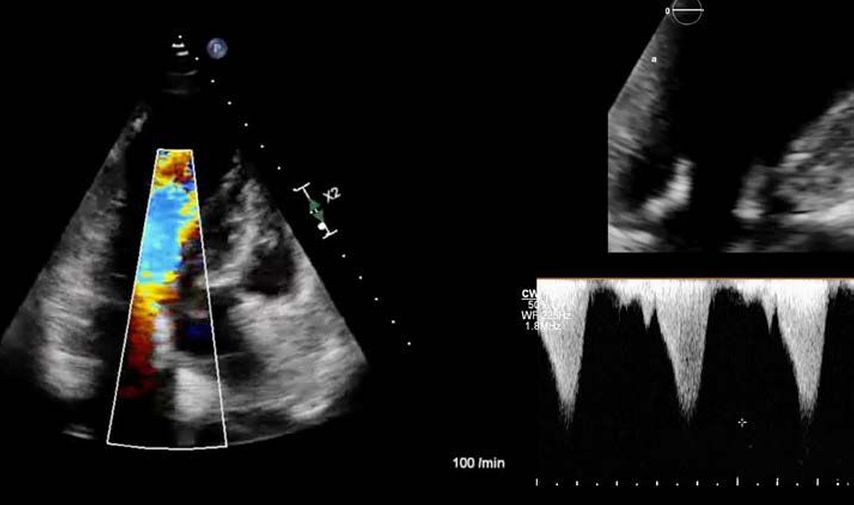

Im Echolabor des Pyhrn-Eisenwurzen Klinikums Steyr wird jede Form der Myokardwandverdickung mittels einer vollständigen Standardechokardiografie untersucht.2 Dabei wird auch ein Fokus auf die kontrastmittelunterstützte Sonografie gelegt, um die tatsächliche Dicke des Myokards zu vermessen.3 Die Verdickung sollte optimalerweise mittels 3D-LV-Massenmessung erfolgen. Die Messung im 2D-Bild ist dahingehend unterlegen. Ebenso wird jede Myokardwandverdickung mittels 2D-„strain imaging“ in der transthorakalen Echokardiografie (TTE) untersucht.4–6 Der „strain“ ist eine Messung der longitudinalen Funktion des Herzens (Video 1).

Bei der hypertrophen CMP gibt es die Besonderheit, dass versucht werden muss, einen Ausflusstraktgradienten (LVOTO) zu messen, da dieser für die Prognose und Therapie relevant ist.1 Eine neue Therapie der hypertrophen obstruktiven CMP (HOCMP) sind kardiale Myosininhibitoren. Diese können zu einem „reverse remodeling“ des Herzens führen und Parameter, wie den „strain“, neben der Reduktion des Ausflusstraktgradienten unter Therapie deutlich verbessern.1,8,9

1. Fall: HCMP vs. HOCMP, männlich 52a

Der erste Fall beschäftigt sich mit einem Patienten mit einer hypertrophen Kardiomyopathie (HCMP). Er gibt eine deutliche Belastungsdyspnoe sowie einen ausgeprägten Leistungsknick an. Es wurde infolgedessen eine Untersuchung mittels standardisierter Echokardiografie inklusive „strain imaging“ durchgeführt. Der globale longitudinale „strain“ (GLS) mit –16% in Ruhe war gering reduziert. Es konnte kein relevanter LVOT-Gradient in Ruhe nachgewiesen werden. In der Belastungssituation (Handgrip, Valsalva, Kniebeugen und als Vorbereitung zur Untersuchung ein ausgiebiges Frühstück und Kaffee sowie ein am Vorabend konsumiertes Bier) konnte bei Kniebeugen mit einer Herzfrequenz von 126/min ein Spitzengradient bis 52mmHg dargestellt werden. Somit ergibt sich die Diagnose einer HOCMP mit einem belastungsinduzierten Gradienten. Bei bereits bestehender und ausgereizter Therapie unter Betablocker besteht die Indikation zur Therapie mittels des kardialen Myosininhibitors Mavacamten (Klasse-IIa-Empfehlung laut ESC).1 Darunter verbesserte sich die klinische Situation des Patienten deutlich, der Patient konnte uneingeschränkt Sport ausüben. Über die Zeit kam es zu einer geringen Reduktion der LV-Masse und einer geringen Zunahme des LV-„strain“. Die Belastungssituation zeigte durchwegs normale „strain“-Werte mit –20% (mit regionaler Reduktion bei Myokardwandverdickung im Sinne einer Hypertrophie). Die myokardiale Arbeit beim konkreten Patientenfall ist ebenso in Ruhe im grenzwertigen und unter Belastung im guten Normalbereich.6,8,9 Der Patient ist derzeit unter 5mg Mavacamten einmal täglich optimal eingestellt. Die EF in Ruhe ist konstant bei 50–55%. In Video 2 werden unterschiedliche Gradienten dargestellt, um eine HOCMP mit LVOTO von z.B. einer Mitralklappeninsuffizienz zu unterscheiden.Die Verdachtsdiagnose wurde mithilfe der Echokardiografie gestellt und durch das septal betonte „patchy“ LGE im MRT bestätigt.1,5